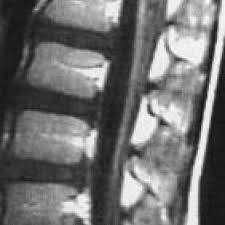

However, it can reveal nerve root enhancement and may be an effective diagnostic adjunct. The severity on mri does not correlate with severity of the clinical condition. Fisher syndrome, a clinical variant of guillain­ barre syndrome characterized by ataxia, are­ flexia, and ophthalmoplegia, brain stem lesions have been described with cranial mr.imaging (8). Its signs and symptoms are similar to those of other neurological disorders and may vary from person to person. Sagittal and axial post contrast t1 fs images shows smooth thickening and abnormal enhancement of the cauda equina and the ventral nerve roots. Moreover, gbs is also associated with any vaccination. Your doctor may then recommend: It is characterized by a triad of ophthalmoplegia, ataxia, and areflexia.

Its signs and symptoms are similar to those of other neurological disorders and may vary from person to person. Sagittal and axial post contrast t1 fs images shows smooth thickening and abnormal enhancement of the cauda equina and the ventral nerve roots. Mri is sensitive, but nonspecific, for diagnosis. The diagnosis is usually established on the basis of symptoms and signs, aided by cerebrospinal fluid findings and electrophysiologic criteria. Clinical presentation is usually characterized by rapidly progressive, ascending, and symmetric paralysis of the extremities. Scott olson / staff / getty images Your doctor is likely to start with a medical history and thorough physical examination. It is the most common cause of rapidly progressive flaccid paralysis.

On csf analysis, the cell count is normal in 85% of patients, and high protein values are seen in 64%. Sagittal and axial post contrast t1 fs images shows smooth thickening and abnormal enhancement of the cauda equina and the ventral nerve roots. Clinical presentation is usually characterized by rapidly progressive, ascending, and symmetric paralysis of the extremities. Fisher syndrome, a clinical variant of guillain­ barre syndrome characterized by ataxia, are­ flexia, and ophthalmoplegia, brain stem lesions have been described with cranial mr.imaging (8). Typically, both sides of the body are involved, and the initial symptoms are changes in sensation or pain often in the back along with muscle weakness, beginning in the feet and hands, often spreading to the arms and upper body. Mr imaging findings in eight patients (three male, five female; With treatment, people may improve more quickly. However, it can reveal nerve root enhancement and may be an effective diagnostic adjunct. Your doctor may then recommend: The most common result is a weakness and numbness that starts at the tips of the fingers and toes and spreads inward toward the body. Moreover, gbs is also associated with any vaccination. Mri is sensitive, but nonspecific, for diagnosis. Immune checkpoint inhibitors (icis) have been increasingly used in the treatment of various types of tumors with favorable results.